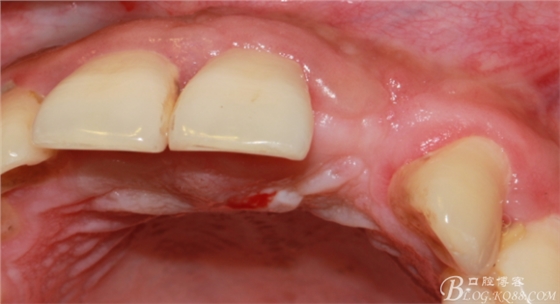

于是我果斷告知患者,手術(shù)失敗了,不能拖延,如不及時(shí)處理,炎癥繼續(xù)發(fā)展會(huì)很快波及鄰牙牙槽骨。患者接受我的建議。切開翻瓣,骨粉及生物膜消失了,骨吸收嚴(yán)重,幸運(yùn)的是,因?yàn)樘幚砑皶r(shí),鄰牙骨支持依然存在。

徹底掻刮。